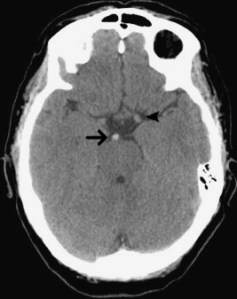

Figure 1 – A Normal CT Head (axial view at the level of the Lateral Ventricles):20

Figure 2 – A Basilar Artery Thrombus shown on Plain CT Head:27